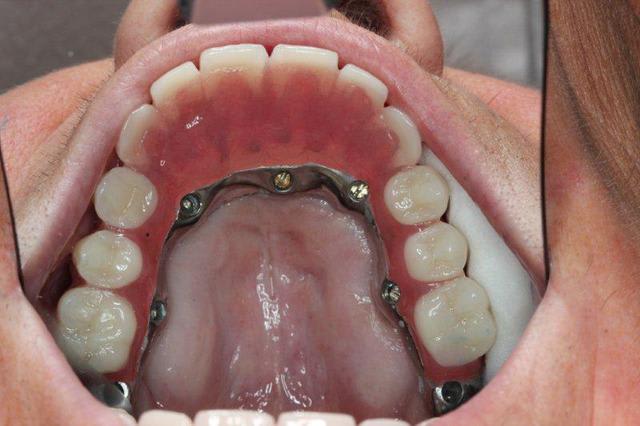

Regarde le provisoire de la MCI : les émergences des plaques au niveau molaires font des bombés hors arcades suite à la pose de piliers monobloc de hauteur 3.5 mm

On pose ces piliers car il faut pouvoir retrouver facilement les têtes d implants 72 h plus tard pour poser la prothèse de transition

1. l hexa te condamne à avoir un puits ds l axe exact du puits hexa... Les vis courtes et à fente te permettent de faire des puits légèrement courbe au niveau antérieur c e qui évite les vis trop gênantes vers vestibulaire qui te contraigent à faire des couronnes scellées sur armature primaire pour cacher les puits vestibulaires ...

3. Aucune nécessité de démonter un fois par an...plus personne ne fait ça car cela "déajuste" perpétuellement ton serrage Juste pano et examen clinique une fois par an